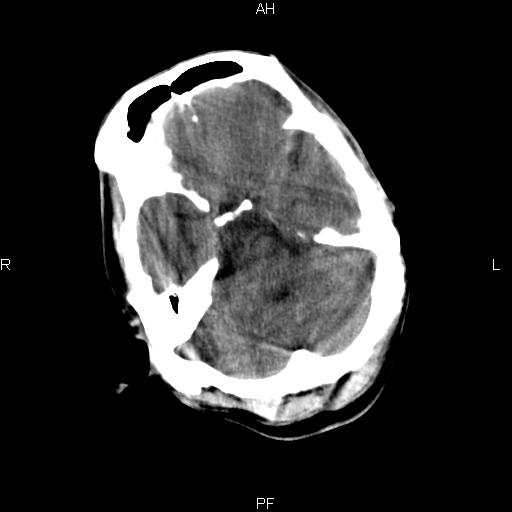

男性,45岁,缄默少语,四肢无力一个月。骨窗未见明确异常。

弥漫性脑白质低密度症

对称性脑白质广泛低密度。有高血压史及大量饮酒史吗?

考虑重度脑白质稀疏症。

双侧弥漫性对称性全累及性(外囊亦有累及)脑白质病

患者病程月余,脑沟裂闭合,第三脑室较窄,提示应该有较明显的脑白质水肿,考虑有持续性炎性病变

综合考虑脑白质感染性或非感染性炎症可能性大,不排除为克雅氏病